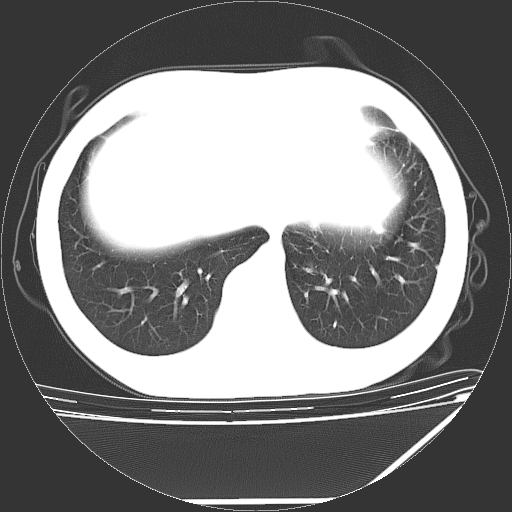

男,13岁,咳嗽、咳痰伴发热一周。

纵隔多发肿大淋巴结,部份有融合改变。双肺血管气管束增厚,以肺门为中心向外周散发,以左肺下叶为明显。考虑淋巴瘤可能性大。不除外原发综合征。

左肺野见淡片状影,病因整体多考虑结核

单纯看片子感觉左侧肺通气不畅,而不像肺内病变引起的纵隔病变。而且纵隔及左肺门都有淋巴结增大。首先还是考虑一下结节病,不排除淋巴瘤!!!